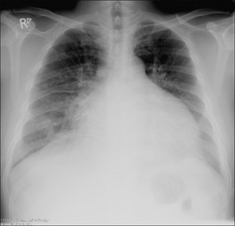

Figure 30.6 Mild haemoptysis. Due to infection. Lobar pneumonia.